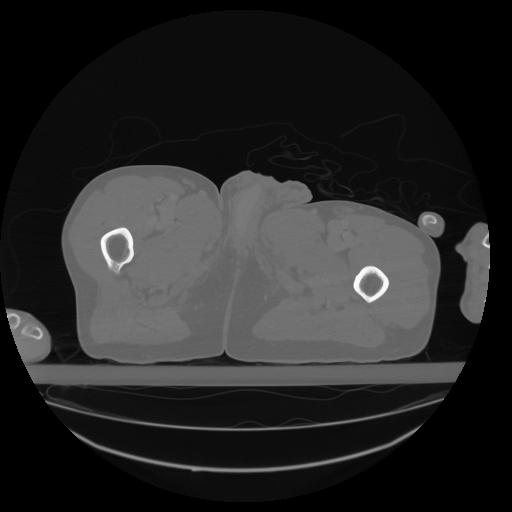

34 CUERPO,CE,Vol,1.0,CUERPO,,